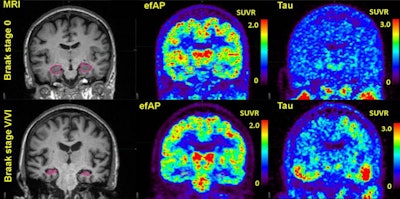

Researchers at the University of Alabama at Birmingham compared early-frame amyloid PET imaging with standard flortaucipir-PET imaging for Alzheimer's disease and found the new method effectively identified brain pathology associated with the disease in three minutes, compared with scans that can take up to three hours.

The researchers found that measurements with early frame amyloid PET within the hippocampus within the first three minutes of brain activity postinjection showed the strongest discriminative ability to stratify for tau positivity (AUC, 0.67-0.89 across tau PET regions) in amyloid-positive individuals. In addition, hippocampal early-frame amyloid PET correlated significantly with global tau-PET tauopathy scores in amyloid-positive patients.